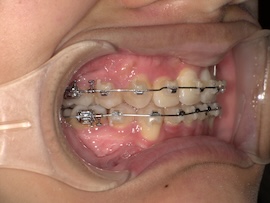

実際に処置をしてもらった直後の写真がこちらです。

まだ麻酔で感覚がないため、唾液が多く見えづらくてすみません。(笑)

意外と近くに埋まっていたそうなので、少し歯茎を切る程度で済んだみたいです。骨は削っていないので腫れもほとんどありません。

その後も歯茎を切った痛みは特別感じることなく、親知らずを引っ張ることに関しても今まで感じた歯の動く痛みと同じくらいでした。ただ全体的な痛みではないため反対側で普段通りの食事はできますし、覚悟していた分全然楽に感じます。(笑)

また、一度だけ歯磨き中に出血してしまって驚きましたが、少し裂けてしまっただけで特に問題ありませんでした。